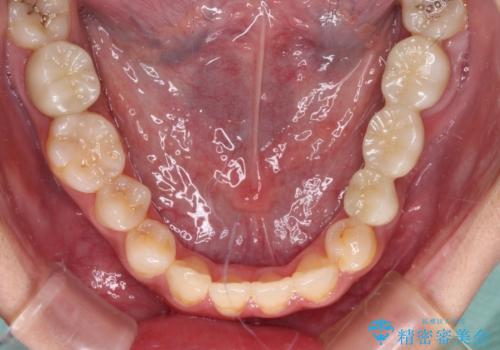

むし歯だらけの奥歯 セラミッククラウンによるむし歯治療

根管治療や歯周外科処置後にフルジルコニアクラウンにて補綴治療することとしました。

再発や他の歯がむし歯となるリスクを低減させるため、日頃からのプラークコントロールと定期的なクリーニングが重要となります。